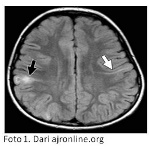

Pasien dengan tumor di otak (Foto 1) biasanya menunjukkan tanda-tanda epilepsi dan atau retardasi mental.

Kriteria diagnosis ini sangat bermanfaat untuk secara meyakinkan memisahkan pasien TSC dan bukan TSC bagi keperluan pemeriksaan lanjutan berupa diagnosis molekuler. Dalam proses penegakan diagnosis ini seringkali dibutuhkan pemeriksaan mendalam menggunakan USG dan MRI untuk mendeteksi adanya tumor pada organ-organ di dalam tubuh.